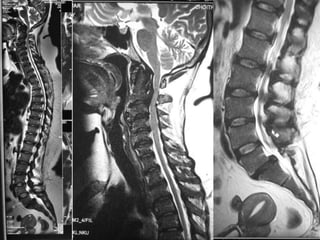

• X-ray of Chest.

• X- Both fore arms - AP

• MRI of Dorsal and Lumbar Spine.

Case report –cont…. • X-ray of Chest. • X- Both fore arms - AP • MRI of Dorsal and Lumbar Spine. • CBC, serum Creatinine, TSH, PTH, Ca, Alk Po4, Urine routine.